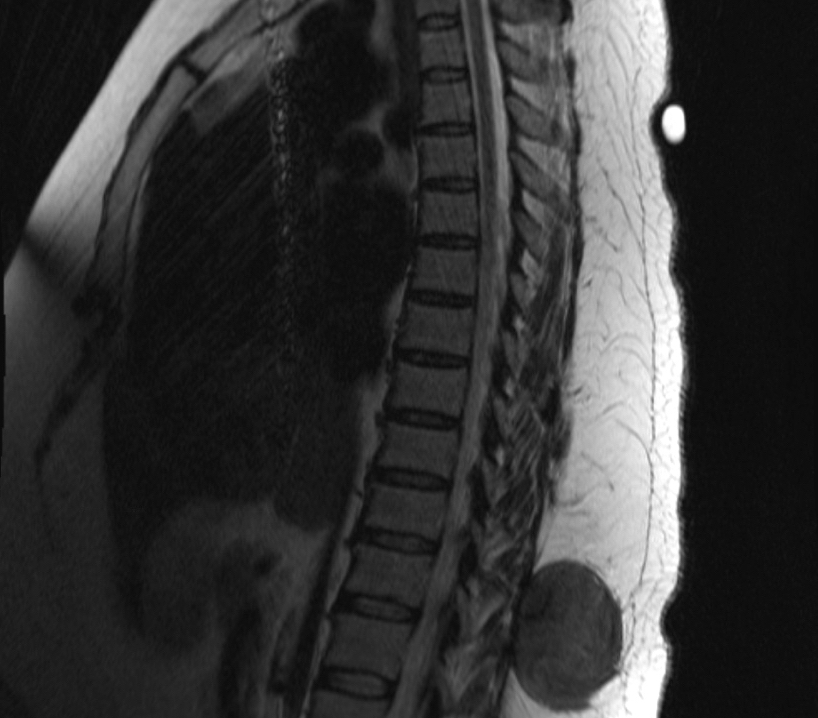

- CT:

- Most commonly used for intraabdominal tumors and associated complications (like small bowl obstruction)

- Soft tissue mass with well to poorly defined margins, variable attenuation and mild to moderate enhancement